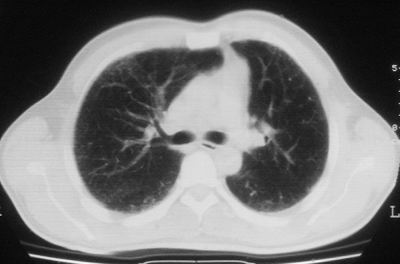

1\\粟粒性肺结核可能性大,支气管肺泡癌不排除

双肺散在小结节影,考虑粟粒性肺结核.肺窗薄扫会更好看些.

考虑粟粒性肺结核

双肺外侧带胸膜下可见网状阴影,考虑轻度肺间质纤维化。

双肺纹理增强并可见网格状影达外带,考虑双肺感染并轻度间质纤维化

1.双肺急性粟粒型肺结核;2.少量腹水.

就这图像考虑间质性肺炎。

肺间质纤维化并肺部感染,结合不能排出,毕竟糖尿病人易合并之,建议结合ppd检查或hrct进一步扫描。